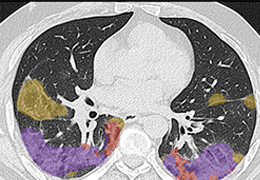

ART-Plan™ Artificial Intelligence Contouring